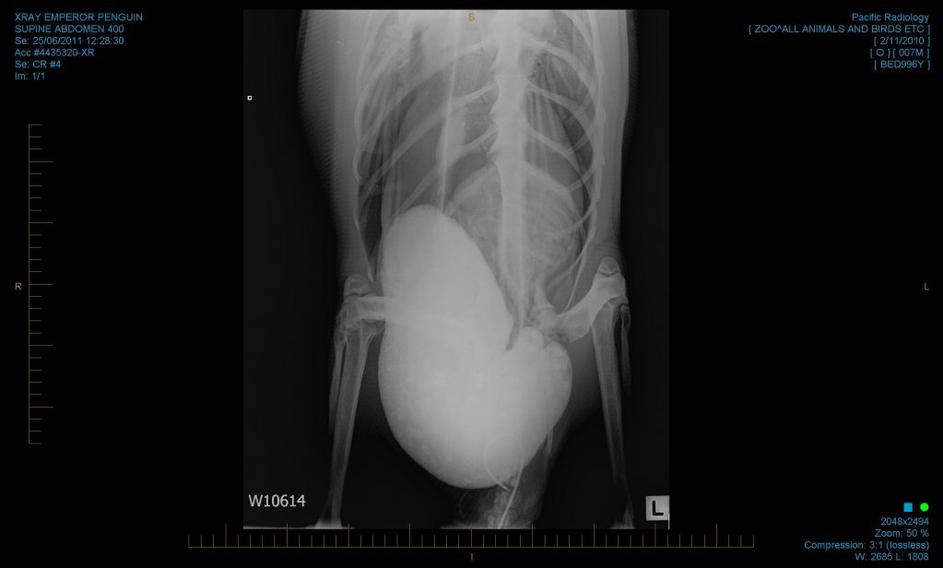

pingvin, operacija, Nova Zelandija, endoskopija Strokovnjaki so kmalu po prihodu pingvina, ki so mu nadeli vzdevek "Vesele nogice", postali zaskrbljeni, saj se je njegovo zdravstveno stanje naglo poslabšalo, bil je dehidriran in izmučen. EPA

Mladi samec je v novem okolju, bistveno toplejšem od svojega naravnega, jedel pesek, ki ga je očitno zamenjal za sneg. EPA